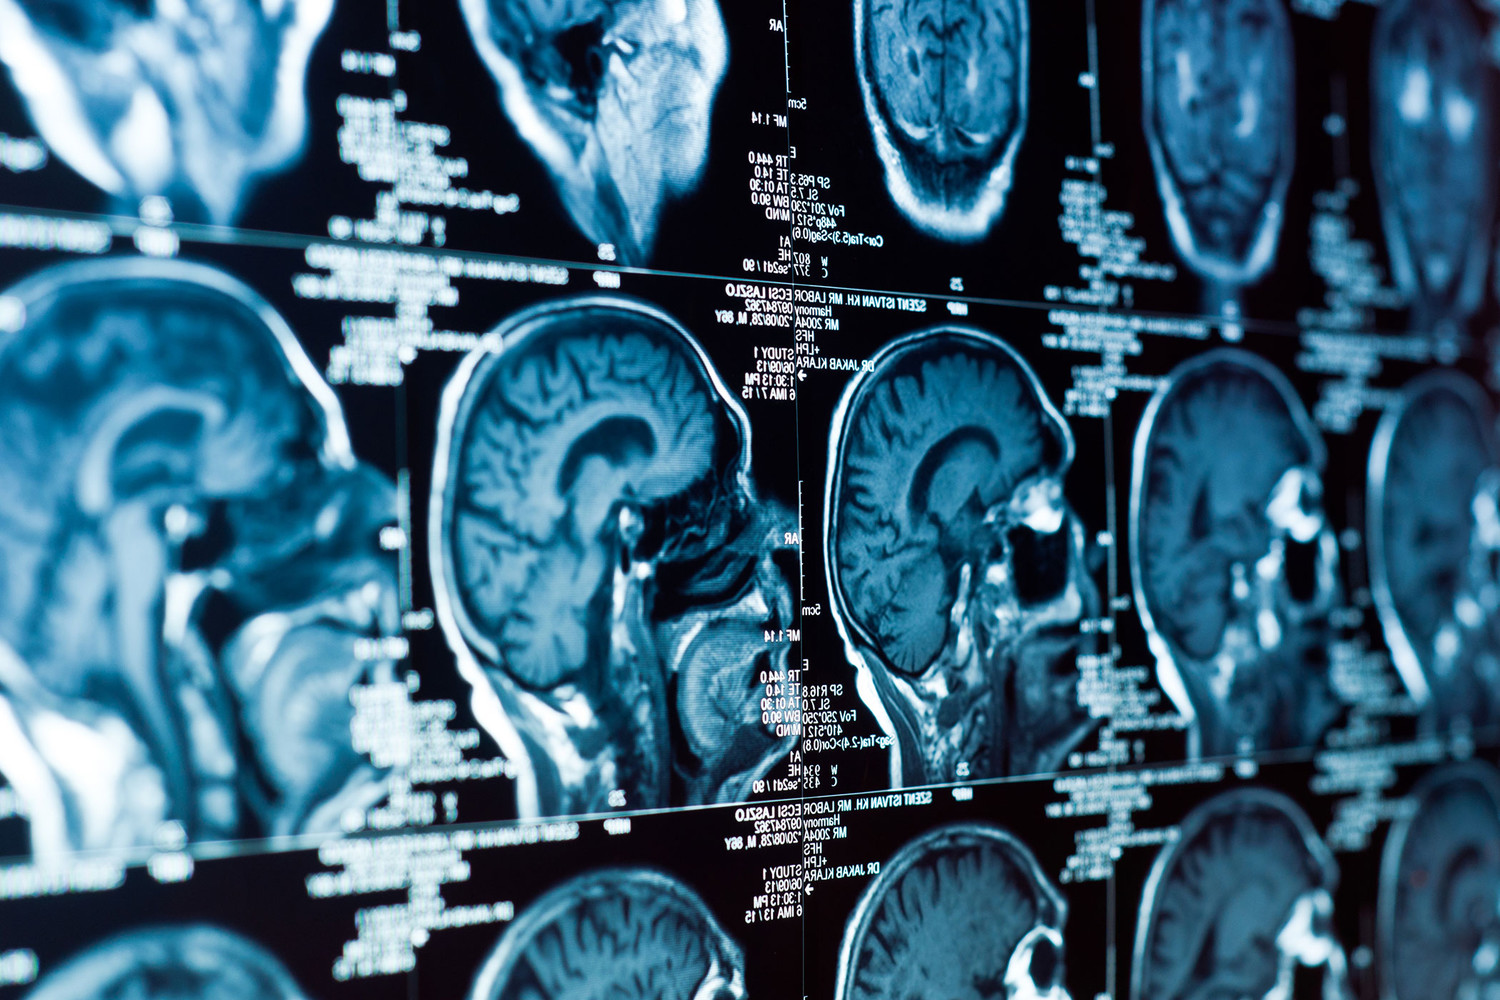

Белок ZIP4 — ключевой фактор агрессивности рака мозга

Белок ZIP4, регулирующий транспорт цинка в организме, оказался важным элементом в развитии глиобластомы — одной из самых опасных опухолей мозга. Это открытие сделала команда исследователей из Университета Оклахомы под руководством профессора Мина Ли. Ученые доказали, что аномальная активность белка провоцирует стремительный рост новообразований.

Глиобластома диагностируется в 45% случаев злокачественных поражений мозга и имеет крайне низкие показатели выживаемости — в среднем 14 месяцев. Исследования показали, что при этом заболевании ZIP4 нарушает баланс цинка, заставляя мозговые ткани поглощать его в десятки раз активнее нормы.